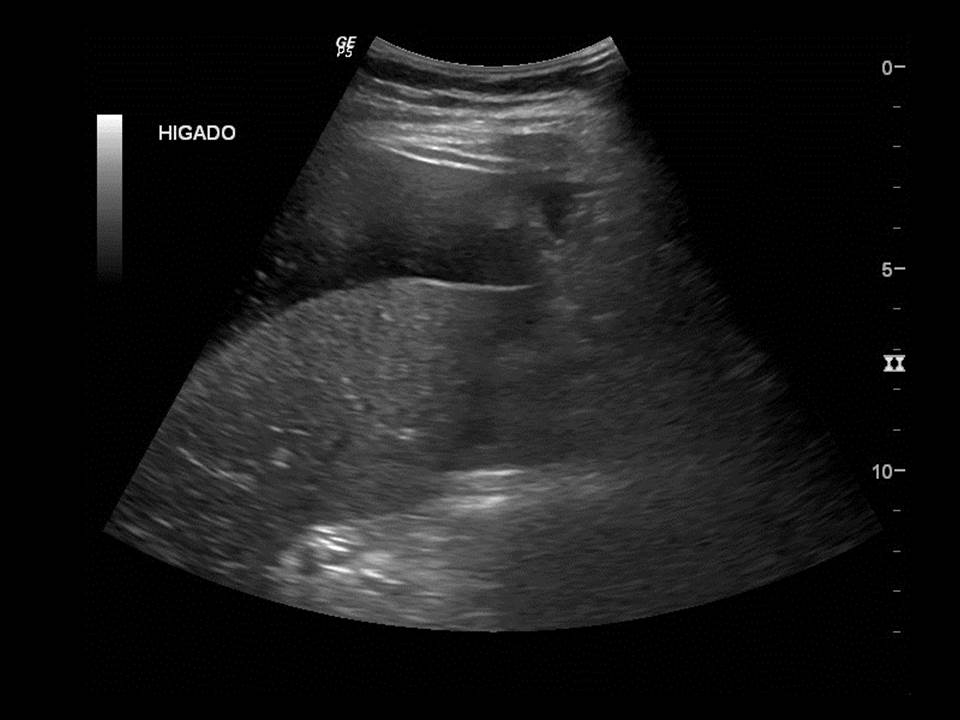

Dolor en hipocondrio derecho

Femenina de 31 años